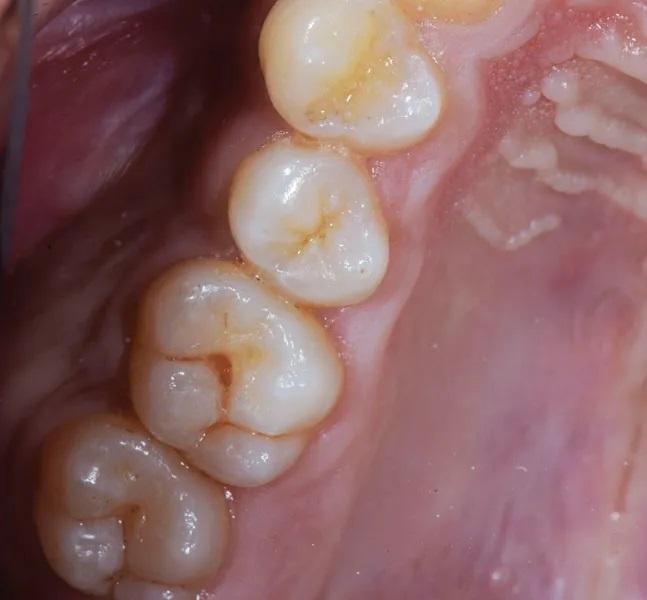

Пациент, мужчина 32 лет, направлен в клинику автора с жалобами на чувствительность зуба в левом верхнечелюстном квадранте к холоду и сладкому. При зондировании выявлен окклюзионный кариес класса 1 в центральной ямке окклюзионных фиссур зуба 2.6 (Фото 1). Выполнены прицельные рентгенограммы для оценки распространенности поражения и исключения вовлечения пульпы. Пациенту разъяснено наличие заболевания; показано прямое восстановление композитной смолой для устранения боли и чувствительности и восстановления функции и эстетики зуба. Пациент согласился; лечение запланировано на следующую неделю.

Фото 1. Пациент жаловался на чувствительность и боль в боковом моляре при воздействии сладких или холодных раздражителей. В зубе 2.6 был обнаружен кариес 1-го класса с окклюзионной стороны.